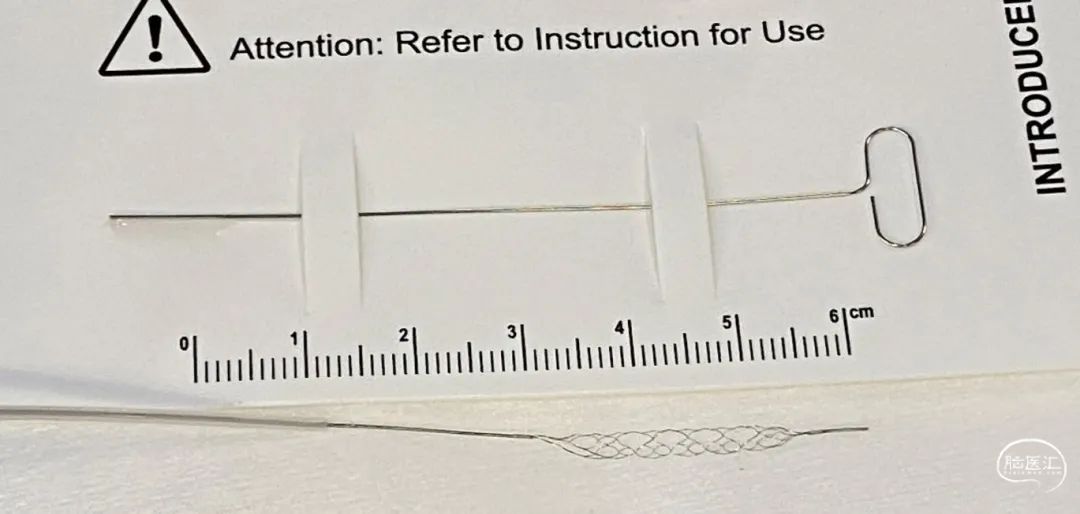

微导管:headway 17

支架:JRecanTM 2.5mm*15mm(瑞康通)

JRecanTM两根铂钨丝缠绕—精准定位,全程显影

JRecanTM交叉螺旋大网格支架—嵌入血栓能力强

JRecanTM远端闭合设计—有效防止血栓逃逸

JRecanTM小尺寸支架—对远端血管损伤小